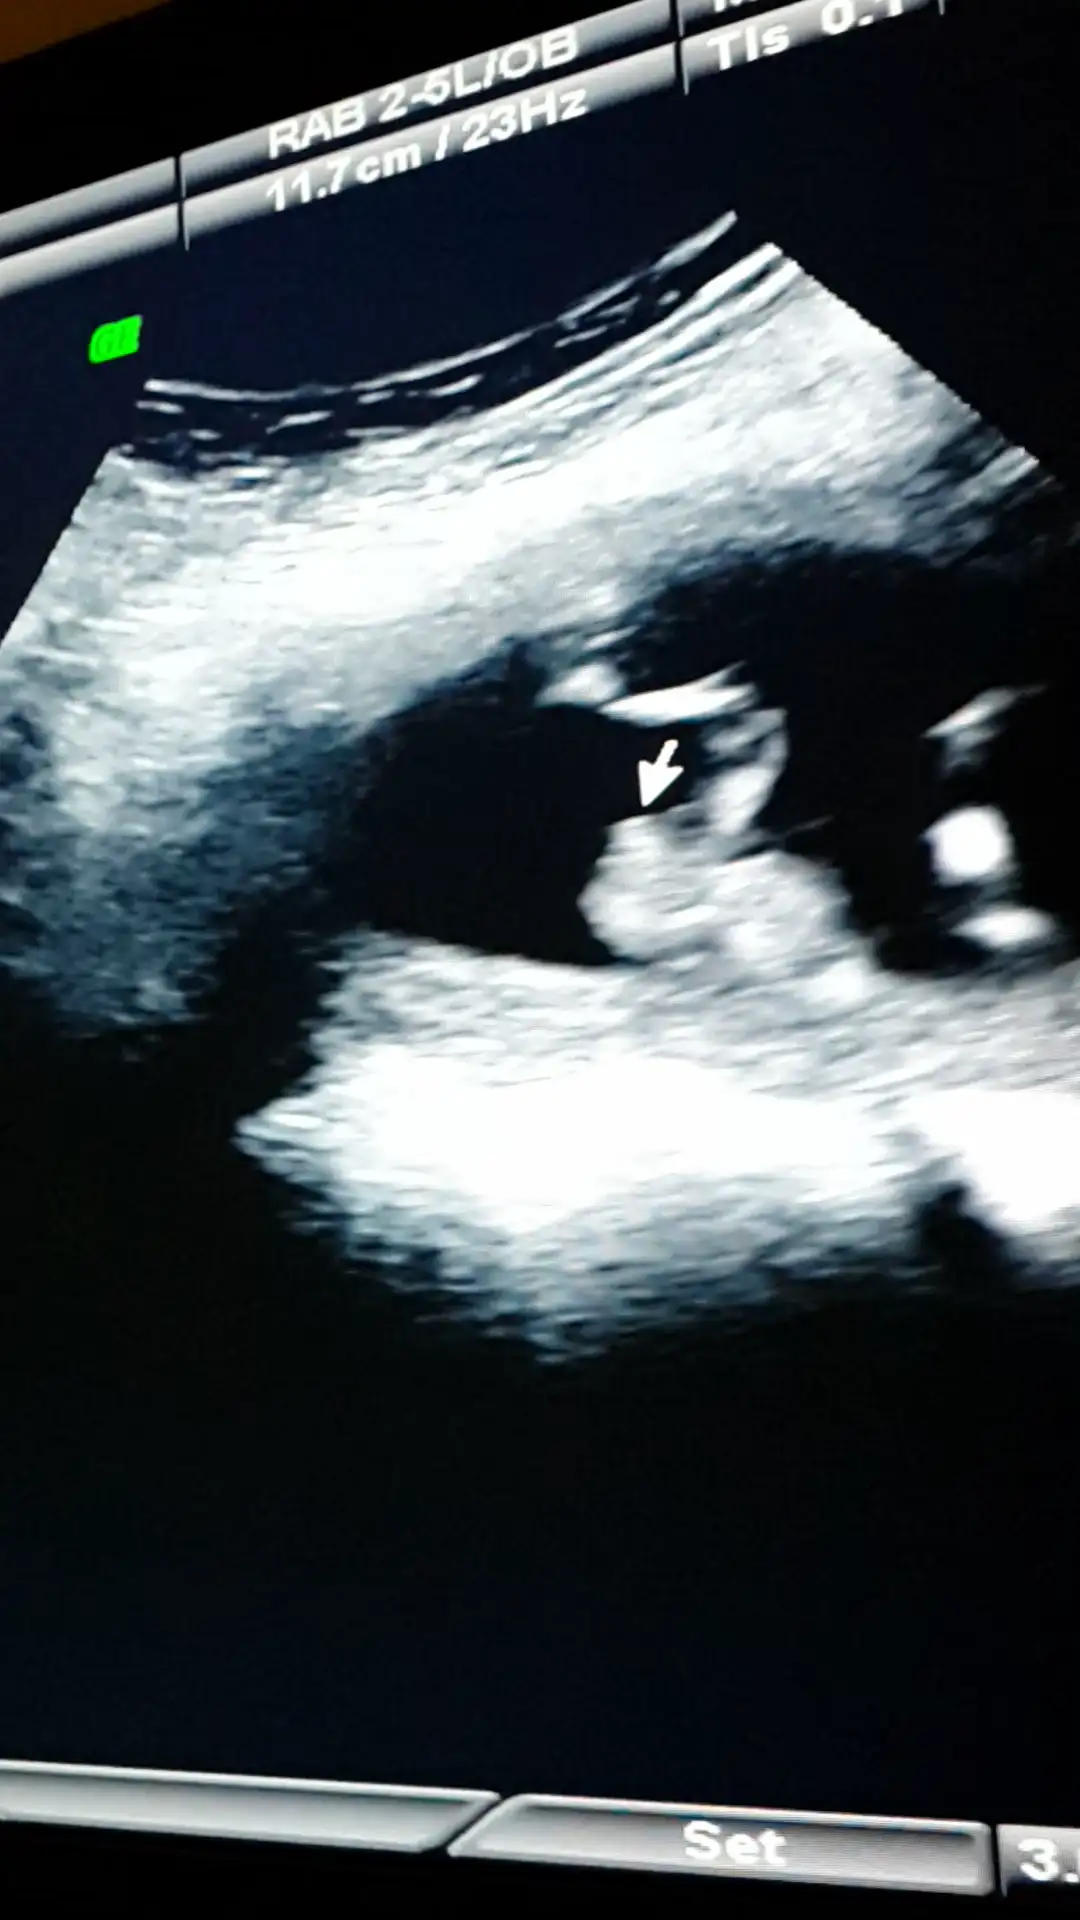

dr soylemeden siz gorun genital nub teorisi ( bebegin cinsiyeti)

Ustteki fotoda erkek gibi eger kordon degilse digerlerinde kiz gibi doktor bisey dedimi

Canim esim bebisi videoya cekmisti ordan kopyaladigim bir resmi ekledim doktorun tam cikintisini isaretleyip gosterdigi yerin resmi. Onuda paylasmak istedim bi bakarsin tekrar doktorla ayni fikirdemisiniz merak ettim senin yorumunuda :anneadayı: